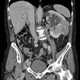

Congenital renal vein thrombosis